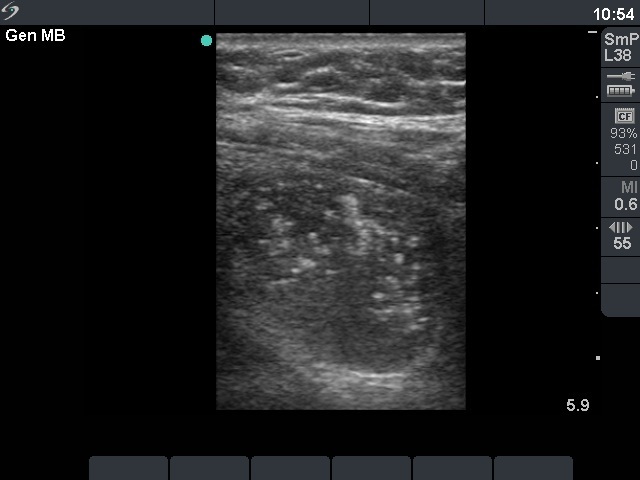

Benign nodular hyperplasia - Case 21. |

First examination (first row of images)

Clinical data: a 56-year-old man was referred for an evaluation of a recurrent nodular goiter. He was operated 14 years ago, histopathology resulted in benign, hyperplastic nodules. He had no complaints.

Palpation: a multinodular goiter.

Functional state: euthyroidism (TSH 0.69 mIU/L, FT4 12.4 pM/L).

Ultrasonography: both thyroids were enlarged and echonormal. There were multiple, moderately hypoechogenic nodules in both lobes. There was a hypoechogenic nodule in the central part of the left lobe which presented hyperechogenic patches containing bright, hyperechogenic punctate granules. This pattern is similar to that observed in medullary cancer. The vascularization was not specific.

FNAC: was repeatedly not diagnostic.